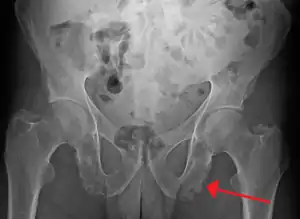

| Enthesopathy of the pelvis likely due to ankylosing spondylitis | |